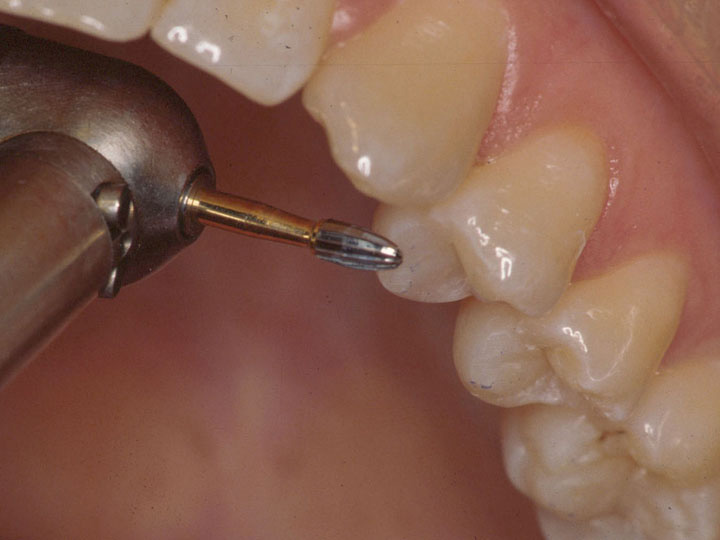

Mastering Occlusal EquilibrationGordon J. Christensen, DDS, MSD, PhD & Valinda Johnston, BS, CDA We are seeing unprecedented levels of cracked natural teeth, TMD, and tooth loss because of occlusal malfunction. Rigid, wear-resi...... |

Occlusal Splints Are Essential!Gordon J. Christensen, DDS, MSD, PhD; Karen Preston, MAEd, RDH, FHEA; & Ric Schwarting, BS Occlusal principles and techniques have become much more essential because of changes in restorative mat...... |